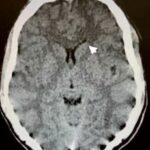

En relación con este tipo de drogas, se puede citar el reporte de un caso de intoxicación de un varón de 16 años por consumo de píldoras de oxicodona. La TC permitió visualizar la hipodensidad en núcleos caudados, así como una rabdomiólisis de etiología inflamatoria o infecciosa (ver Imagen 14). El paciente presentó otros signos como escasa coordinación, pérdida de conocimiento y dificultad para respirar, que se resolvió en pocos días con intubación y asistencia ventilatoria.(23)

En el caso que se viene ilustrando, la RM mostró T2 difuso con hiperintensidades en el cuerpo calloso bilateral frontal y parietal, así como lesión difusa de la sustancia blanca del cerebelo. Se localizaron áreas de difusión restringida en los ganglios basales bilaterales, lo cual tenía relación con la pérdida neuronal mediada por estrés oxidativo (ver Imágenes 15 y 16). El tratamiento permitió la recuperación progresiva del habla y la orientación de la persona. (23)